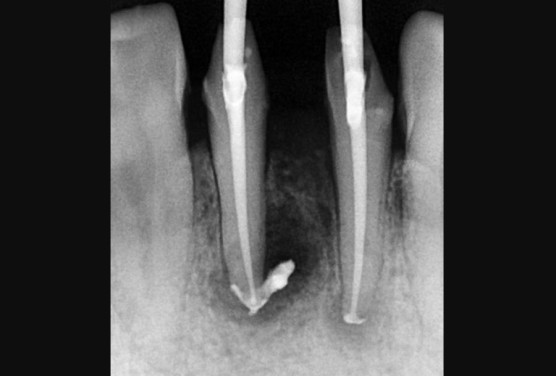

[신경치료 중 뿌리 끝 염증 사진]

신경치료 과정의 사진이며, 뿌리끝 염증이 선명하게 보입니다.

사이즈는 1cm 정도 되며, 뼈이식을 할수도 있겠지만, 많이 언급드렸던 마법의 비약 MTA를 사용합니다.